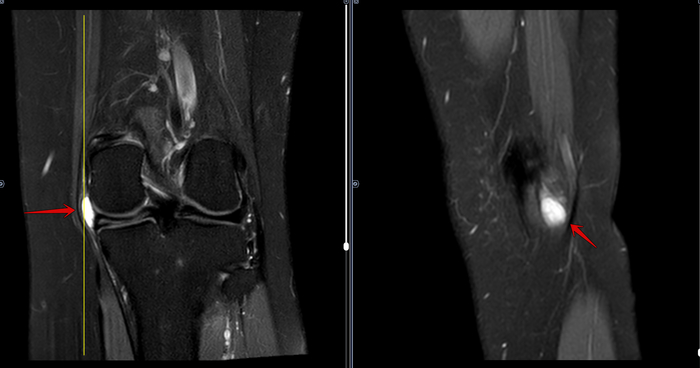

МРТ-Повреждение мениска коленного сустава Stoller 3a⁠⁠

6 месяцев назад

В анамнезе-возникновение болей в левом к/с после интенсивного занятия спортом.

Описание: В структуре внутреннего мениска левого коленного сустава определяется линейный продольный косогоризонтальный патологический МР-сигнал от повреждения с распространением на дистальную суставную поверхность в области тела, заднего рога (соответствует IIIа ст. по Stoller). В области заднего рога медиального мениска определяется многокамерная киста, размерами 1,6х0,7х1,5 см.Целостность крестообразых связок сохранена.В области энтезиса сухожилия медиальной головки икроножной мышцы определяется утолщение, разволокнение.В области сухожилия полуперепончатой мышцы определяется многокамерное жидкостное образование неправильной формы, размерами 1,0х2,8х4,0 см (киста Бейкера).Краевых остеофитов нет.Интенсивность сигнала от клетчатки Гоффа без особенностей. Убедительных данных за патологические изменения остальных видимых мягких тканей не получено.

Заключение:

МР картина повреждения внутреннего мениска (IIIа по Stoller) левого коленного сустава; интерстициальное повреждение внутренней коллатеральной связки; энтезопатии сухожилия медиальной головки икроножной мышцы. Умеренный синовит, супрапателлярный бурсит. Киста заднего рога медиального мениска. Киста Бейкера.